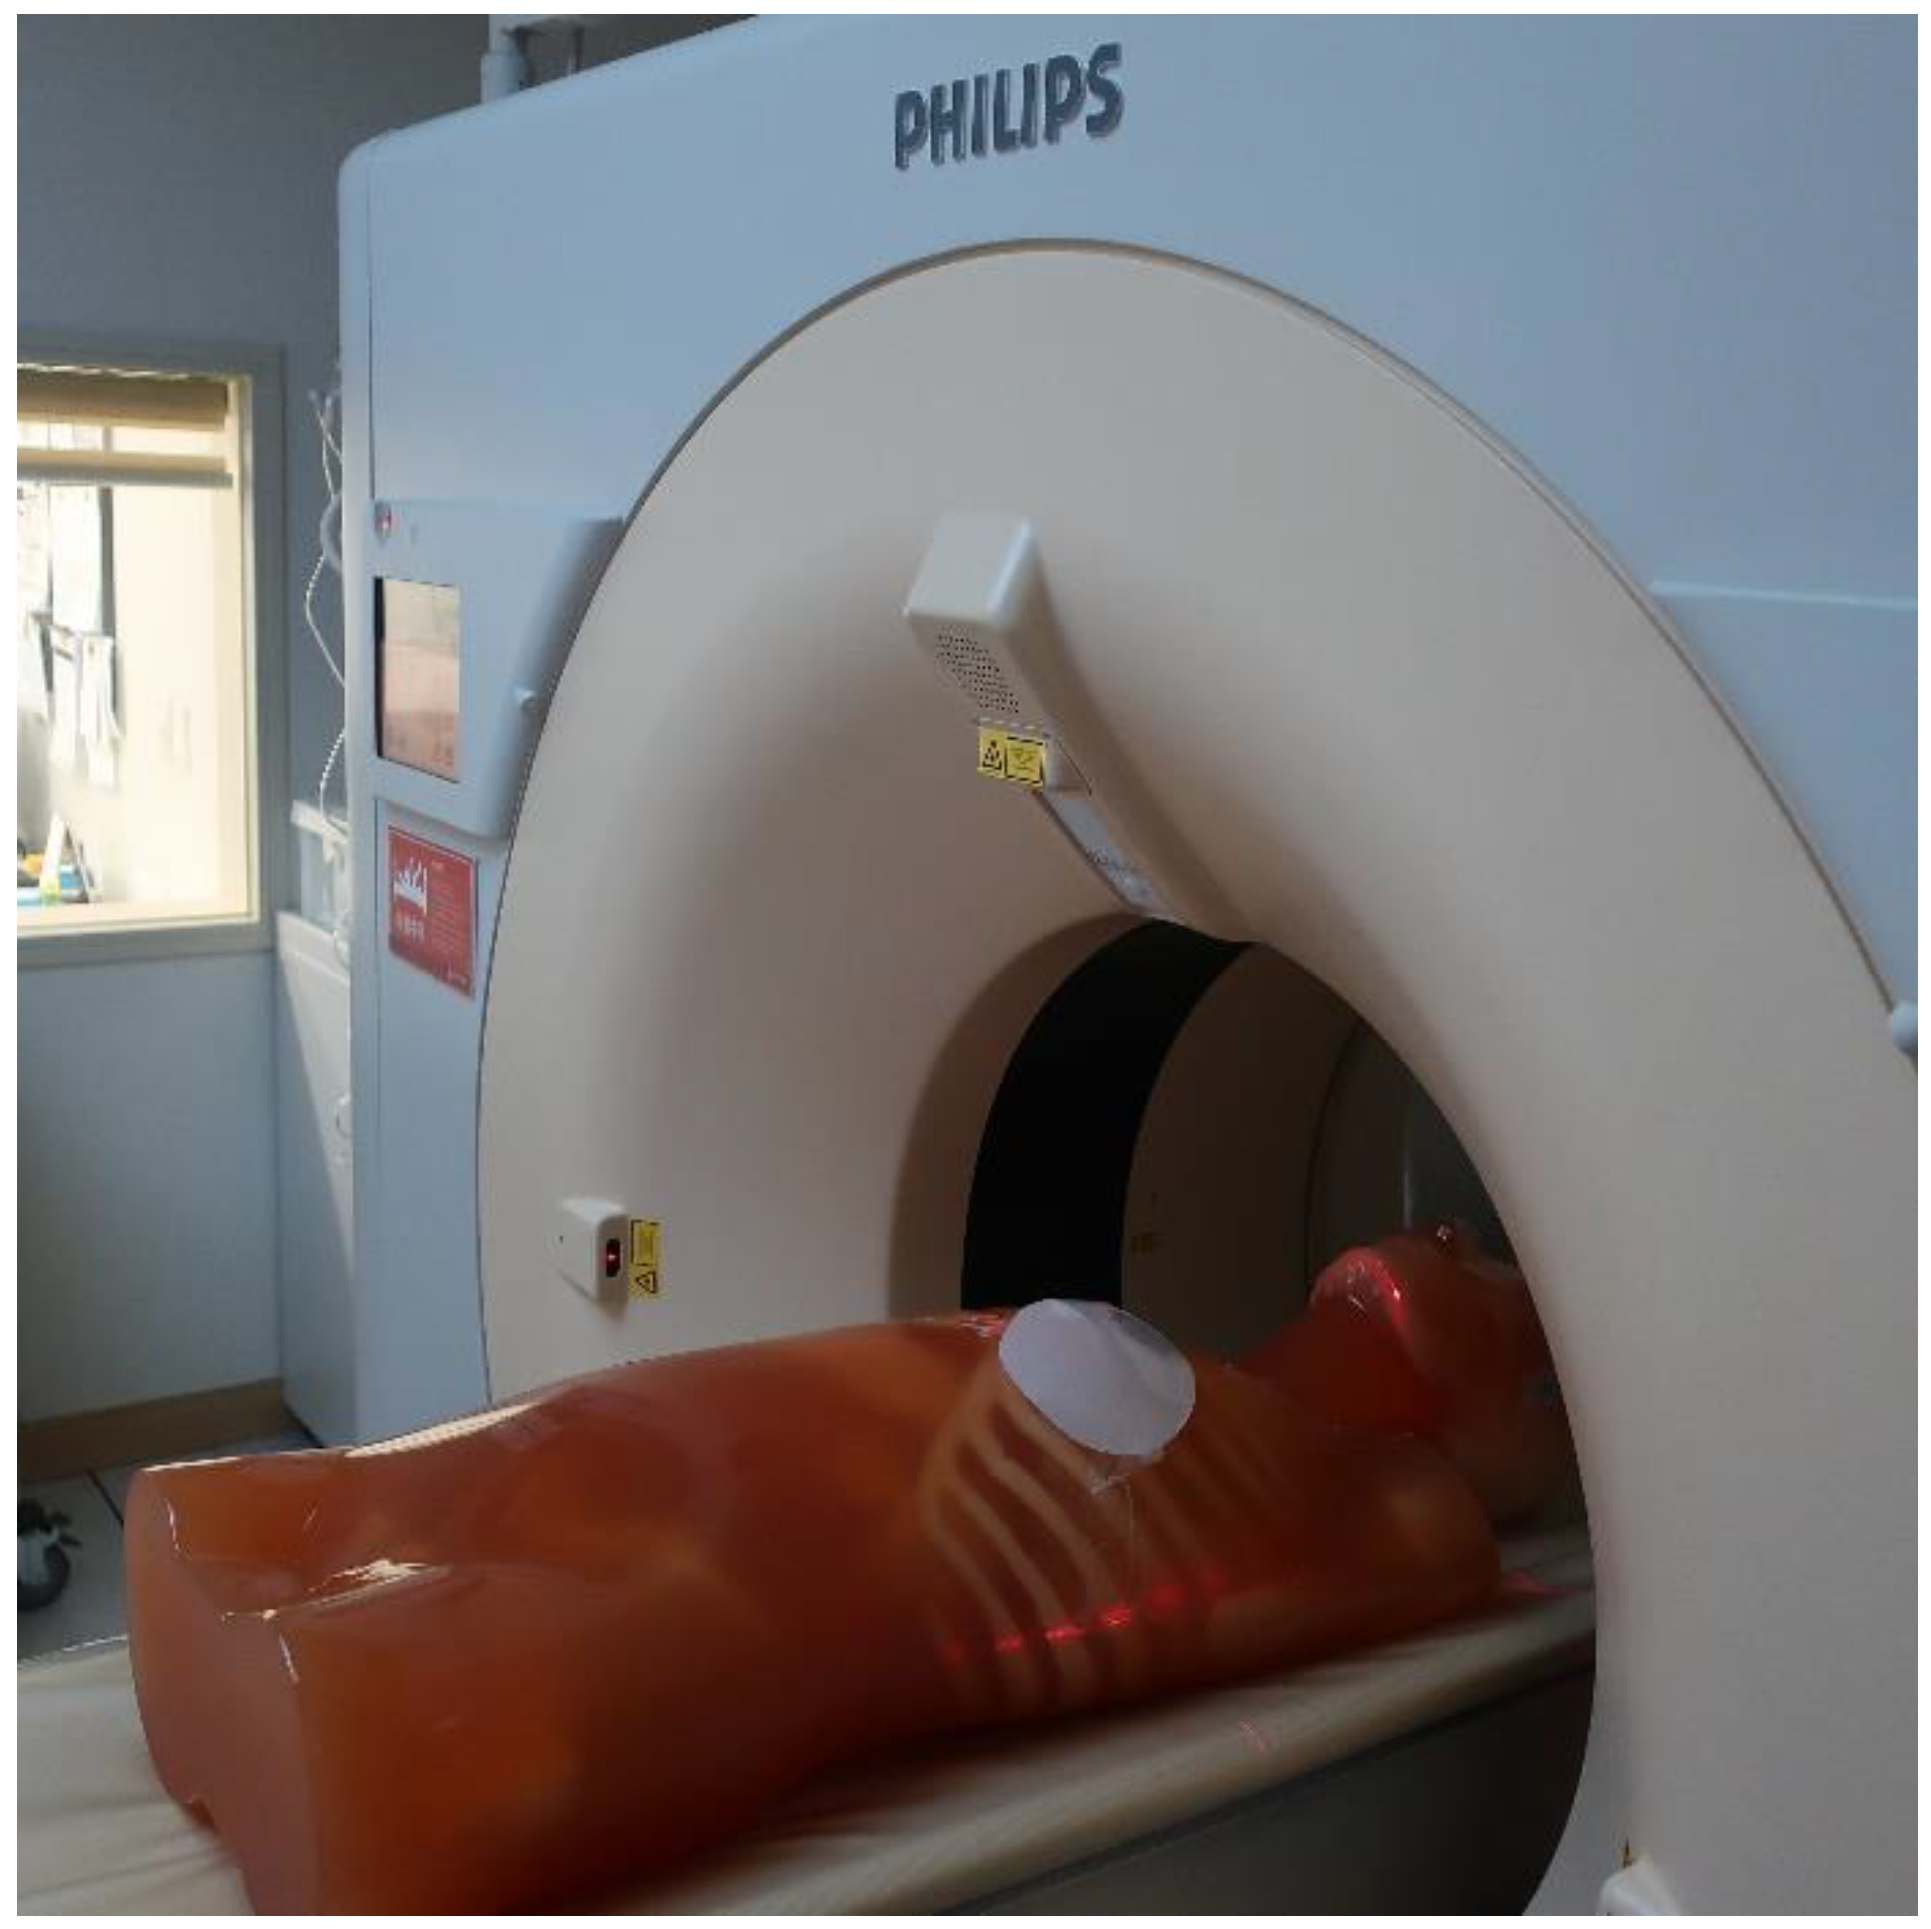

2.2. Computed Tomography Simulation